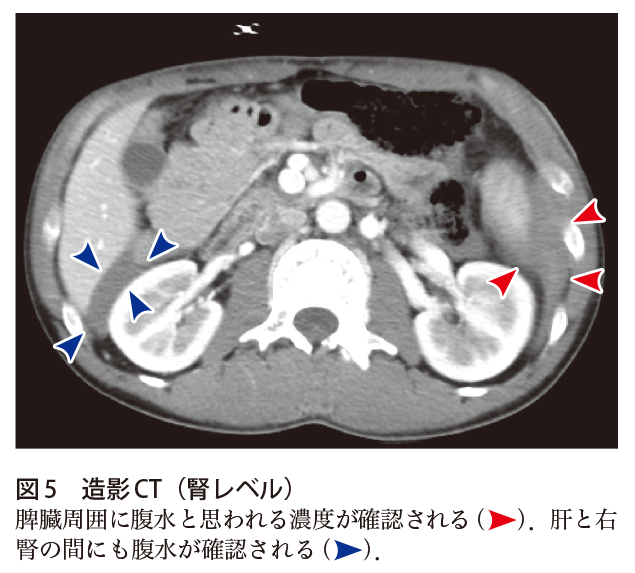

犬 腹水 画像-画像を中心に(腹部編) KKawashima 19年2月19日 引き続き画像関連について、腹部を中心にピックアップします。 だーっと書いたので、まとまっていませんが宜しくお願い致します。 直前で申し訳ありません。 画像引用:長尾大志,レジデントのためのやさしイイ胸部画像教室,p81 立位では、肺の下のほうに胸水が溜まるので (液体は下のほうにたまり) 、CP angle dullとなってわかります。 ただし、少量の胸水の発見には、正面のレントゲン画像はあまり役に立ち